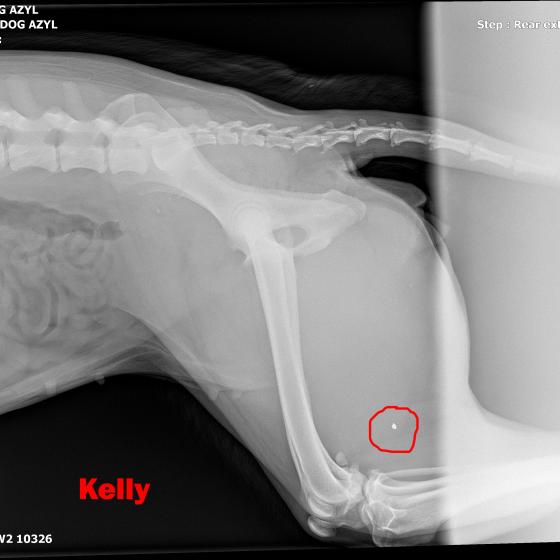

KELLY - Vzali sme ju z ranča, kde boli zvieratá v hororových podmienkach. Neudrží sa na zadných nohách. Môže to spôsobovať hneď niekoľko faktov.

V ľavej packe, medzi druhým a tretím prstom mala brok...

V ľavej packe, medzi druhým a tretím prstom mala brok (treba si to predstaviť, ako keď máte kamienok v topánke a nech stúpate akokoľvek, vždy Vás tlačí. Lenže to je len kamienok a nie cudzí predmet v živom tkanive. Tú bolesť si radšej ani nepredstavujte.) V tej istej nožičke, v oblasti zadnej strany kolena bol ďalší brok, ktorý jej tiež prekážal pri narovnaní nohy. Prvým krokom bolo odstránenie týchto dvoch brokov, ktoré pravdepodobne spôsobovali najväčšie ťažkosti. Operácia sa konala 10.5.2020, dopadla výborne, Kelly sa zotavuje.

Píšeme ale "pravdepodobne" preto, lebo Kelly má tiež problém s krížovým väzom v kolene, ktorý má známky deformácie a má tiež hypointenzitu disku (to znamená, že má na platničke medzi stavcami pruh, ktorý vyčnieva a tlačí na miechu). Veríme, že vsetci strážni anjeli pri nej budú stáť a zvládne sa zotaviť, aby si mohla užívať taký život, aký mala žiť od narodenia. My sme pri nej, zabezpečíme jej všetko potrebné! Za diagnostiku, MRI a chirurgiu máme dve faktúrky, v celkovej výške 762,05€.